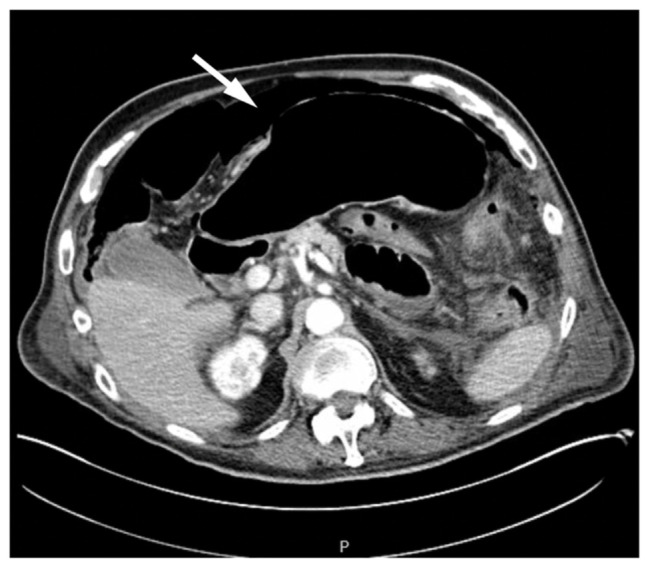

肺癌通常在晚期被诊断出来,经常转移到肝脏、肾上腺、大脑和骨骼等器官。然而,胃肠道转移,特别是小肠,是罕见的。我们报告一个病人谁提出了穿孔的小肠,需要紧急剖腹手术。影像学提示感染过程,但随后的检查显示空肠穿孔和低分化肺癌。尽管有可能接受单独的免疫治疗,病人还是选择了临终关怀。本病例强调了肺癌作为胃肠道并发症的非典型表现,并强调了在鉴别小肠穿孔时保持恶性肿瘤的重要性。

Lung cancer is often diagnosed at advanced stages frequently metastasizing to organs like the liver, adrenal glands, brain and bones. However, gastrointestinal metastasis, especially to the small intestine, is rare. We report a patient who presented with a perforated small bowel, requiring emergent laparotomy. Imaging suggested an infectious process, but subsequent workup revealed jejunal perforation and poorly differentiated lung cancer. Despite being a candidate for immunotherapy alone, the patient opted for hospice. This case emphasizes the atypical presentation of lung cancer as a gastrointestinal complication and underscores the importance of keeping malignancy in the differential for a perforated small bowel.